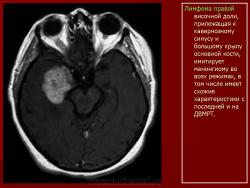

Лимфомы головного мозга.